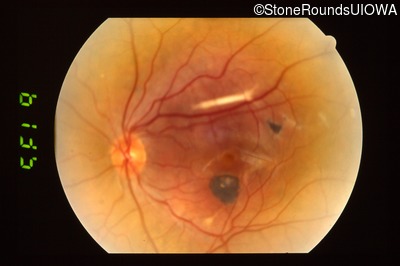

Visit at age: 16 years

Fundus Photography - Right - unknown

Exemplar

Fundus Photography - Left - unknown

Visit at age: 31 years

Fundus Photography - Right - 20/40 -1

Fundus Photography - Left - 20/20 -2